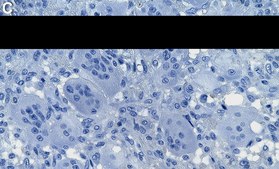

Immunohistochemistry (Paraffin) Analysis: A 1:100 dilution from a representative lot detected Histone H3.3 G34W in Human bone giant cell tumor tissue sections.